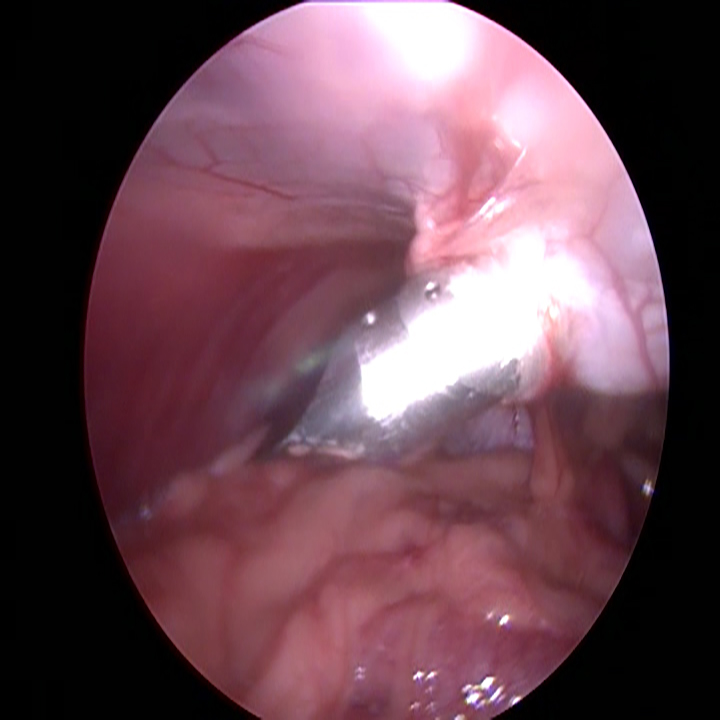

Wanneer alle trocars geplaatst zijn, kantelen we de operatietafel naar voren en leggen we de patiënt op haar zij. Dan gaan we op zoek naar de linker eierstok. Doordat de milt eroverheen ligt kan dit soms wat meer moeite kosten. Eenmaal gevonden, branden we de ophangbanden en bloedvaten van het ovarium door. Hierbij moet ervoor gezorgd worden dat er ver genoeg van de nieren en de buikwand af gewerkt wordt, om hitteschade te voorkomen. De eierstok wordt via het gat bij het bekken verwijderd. Na het controleren van de plek waar de eierstok verwijderd is en na het opnieuw plaatsten van de achterste trocar, wordt de andere kant gedaan.